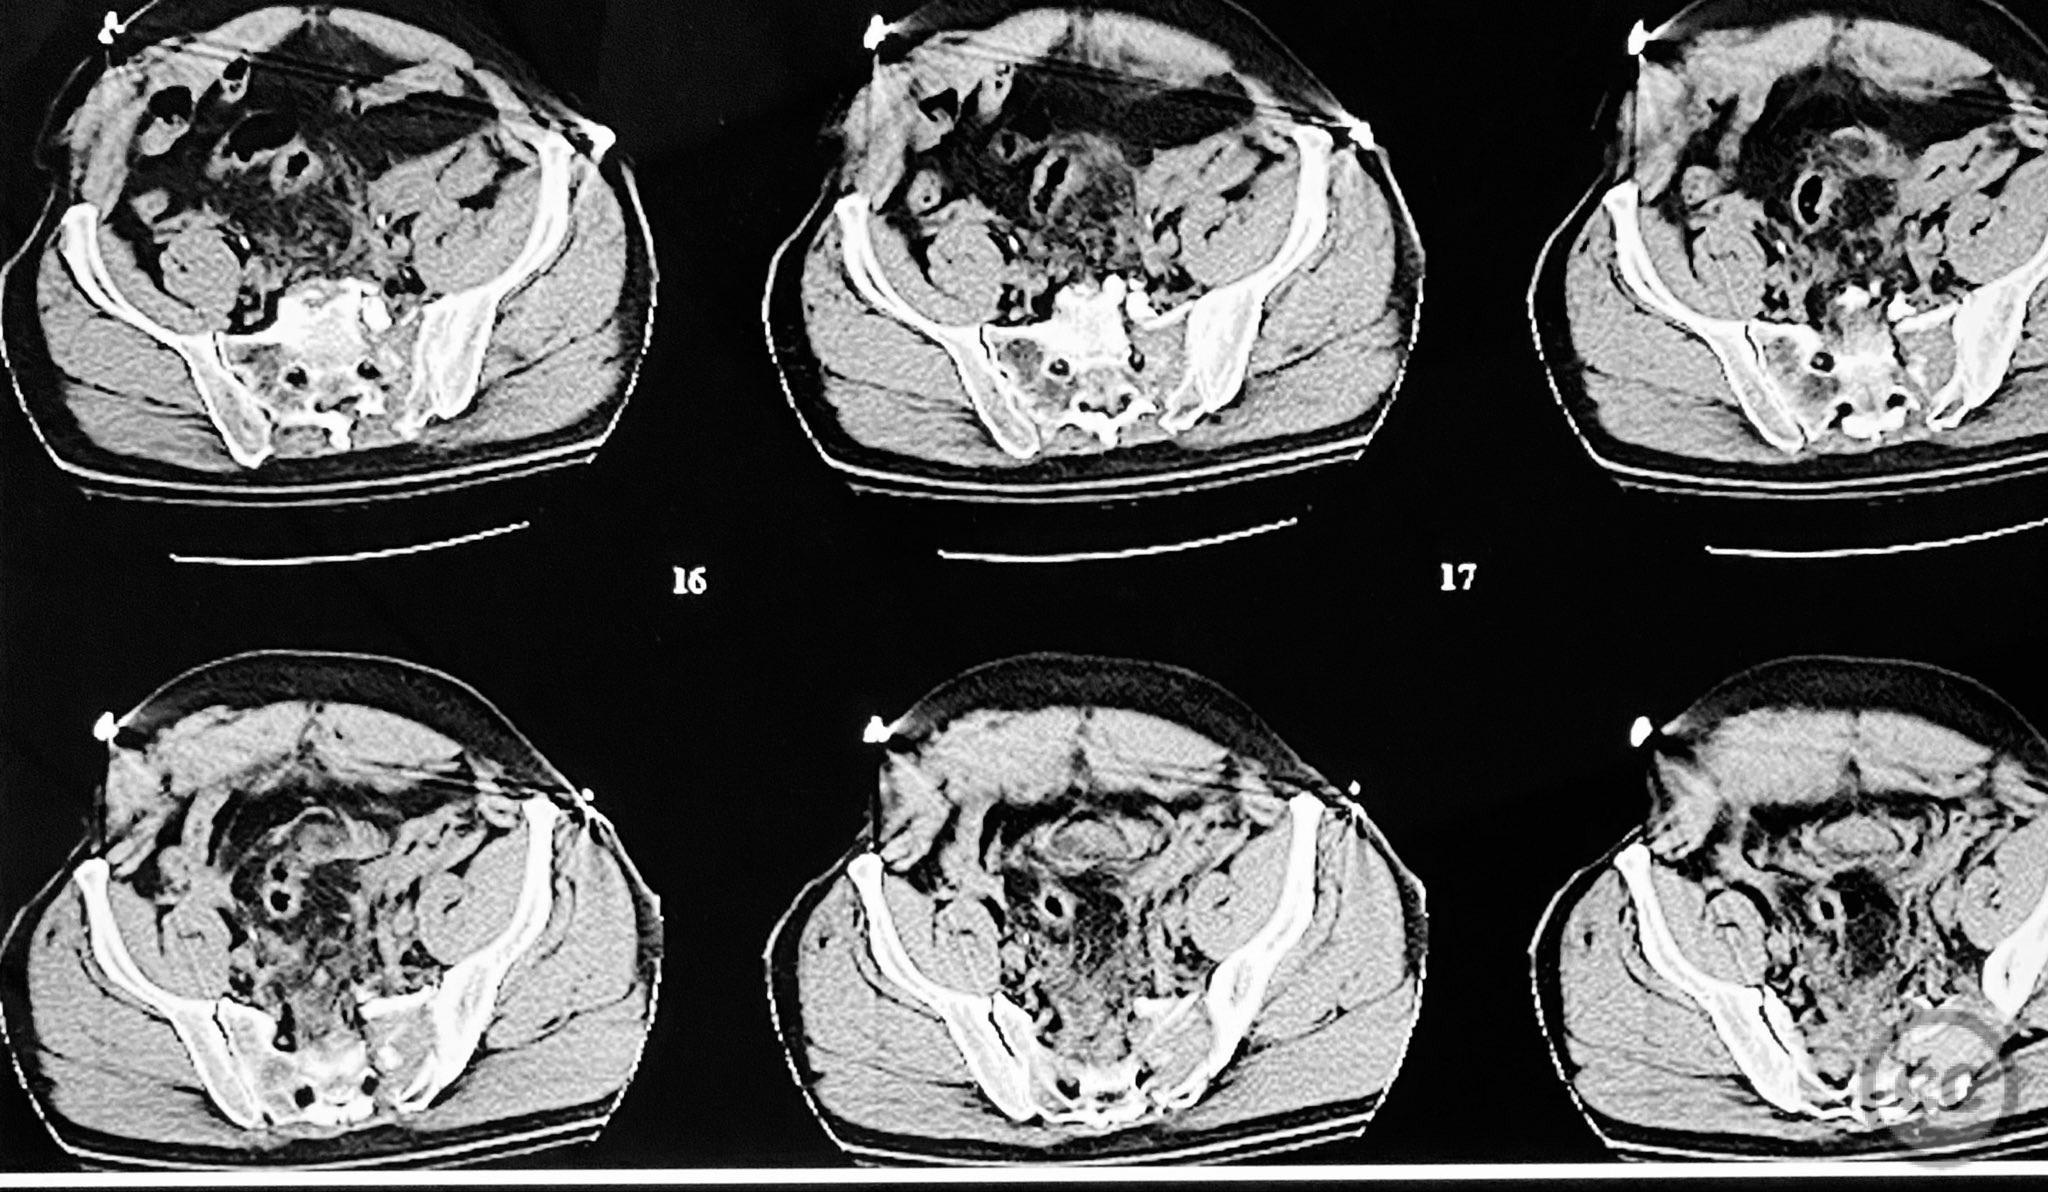

Clinical and radiological findings:  A 54-year-old male presented following a motor vehicle accident with pelvic pain. He was haemodynamically stable and neurologically intact on admission. Initial anteroposterior pelvic radiograph demonstrated disruption of the symphysis pubis, fractures of the left superior/inferior pubic rami, and a left sacral fracture. Circumferential pelvic sheeting improved patient comfort and reduced hemipelvic displacement. Skeletal traction was considered but not yet applied. Computed tomography revealed comminution and displacement of the left sacral fracture, as well as detailed characterization of the anterior ring injuries. AO/OTA classification: 61-C1.3 (displaced, combined anterior and posterior ring injury with complete instability). Young-Burgess classification: APC III.

The posterior reduction was facilitated by direct visualization of the dorsal sacral cortex, allowing precise assessment and clamping of the comminuted fragments prior to screw fixation. The iliosacral screws were placed without cannulated instrumentation longer than 130mm, reflecting historical implant limitations at the time of surgery. Postoperative CT confirmed satisfactory reduction and fixation of the posterior ring, though suboptimal positioning of iliosacral screws was noted (contained within the osseous fixation pathway but not optimized for maximal safety or precision). The anterior ring was subsequently addressed in a staged fashion, with anatomical reduction and stable fixation achieved via open technique. This case highlights technical challenges in achieving optimal screw trajectory and length, particularly with historical implant constraints, as well as the importance of staged management in complex pelvic ring disruptions.